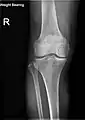

Fractures

Knee fractures are rare but do occur, especially as a result of a road accident. Knee fractures include a patella fracture, and a type of avulsion fracture called a Segond fracture. There is usually immediate pain and swelling, and a difficulty or inability to stand on the leg. The muscles go into spasm and even the slightest movements are painful. X-rays can easily confirm the injury and surgery will depend on the degree of displacement and type of fracture.

The degree of varus or valgus deformity can be quantified by the hip-knee-ankle angle,[33] which is an angle between the femoral mechanical axis and the center of the ankle joint.[34] It is normally between 1.0° and 1.5° of varus in adults.[35] Normal ranges are different in children.[36]

X-ray

Knee X-ray

Knee X-ray (weight bearing)

Knee X-ray (weight bearing, flexion)